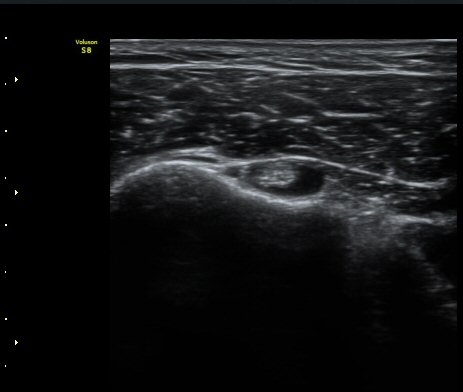

¾î±ú ¾Õ À̵ιڱ٠Ⱦ´Ü¸é°Ë»ç¿¡¼­ ÀÌºÎ¹Ú±Ù°Ç °í¶û ¾Æ·¡ ºÎÀ§¿¡¼­ À̵ιڱ٠ÀåµÎ ÁÖÀ§¿¡

¼ö¾×Àú·ù°¡ °üÂûµÈ´Ù(±×¸² 1, 2). °ß°©ÇÏ±Ù°Ç Á¾´Ü¸é°Ë»ç¿¡¼­ °ß°©ÇϱٰÇÀÇ °üÀý³»ºÎÀ§(±×¸² 3)